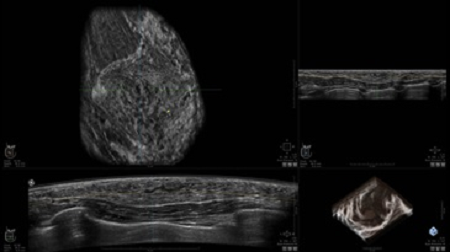

GE INVENIA ABUS – это современный УЗИ аппарат, который создан для точной и эффективной диагностики сканирования с высокой плотностью молочных желез. Выявляемость патологий раковых и предраковых стадий заболевания составляет 55%, что в конечном счете позволяет ставить врачу точные и своевременные диагнозы. Традиционные методы использования маммографии не показывают такой выявляемости, ограничиваясь лишь 3-38%.

УЗИ-аппарат GE INVENIA ABUS позволяет проводить максимально операторонезависимые процедуры, что значительно снижает риск неправильной постановки диагноза и сопутствующие издержки на обработку информации. Система готовит отчет в течение 3-х минут после сканирования, это безусловное преимущество по сравнению с обычным УЗИ сканером.

• датчик с изогнутой апертурой для качественного исследования

• сканирование одной грудной железы в трех проекциях не более 60 сек.;

• обработка результатов за три минуты.

• Получение объемных 3D изображений с возможностью покадрового просмотра

• Получение изображений в поперечной плоскости (в реальном времени) и в коронарной плоскости (статическая, для указания нахождения соска)

• Отображение объемных 3D ультразвуковых изображений, которые состоят из традиционных поперечных и воссозданных коронарных и сагиттальных проекций

• Возможность отображения полного 3D изображения